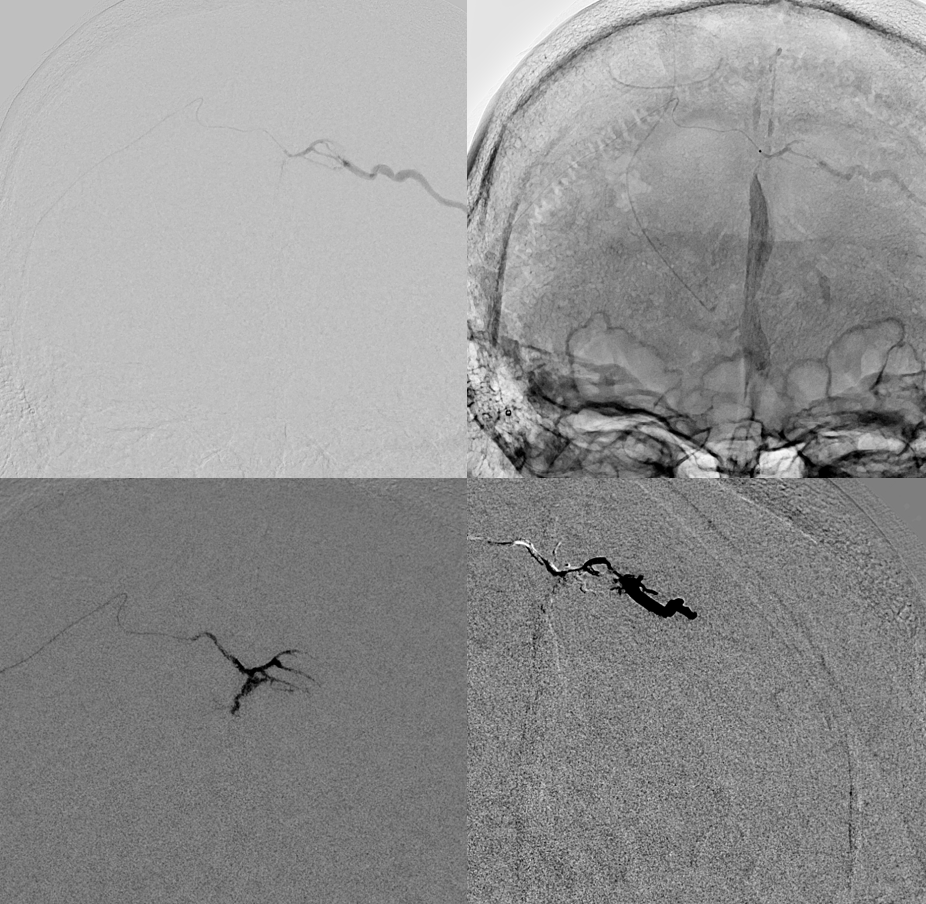

Supply is from right primarily. Note something unusual about the MMA — hard to see here

Right ECA — also unusual appearance of the MMA

Here is the detail. There is a short segment proximal MMA occlusion, with reconstitution from the anterior deep temporal

There are a number of options present here. One is to try to recanalize the MMA — the advantage is that if it does not work out, nothing bad happens.

Recanalization is successful with Aristotle 14 standard and headway duo, supported by Phenom Plus and Benchmark (radial access)

The rest of the way is not easy either — tons of tortuosity. This is addressed with a hybrid .07, and phenom plus in the MMA beyond the recanalized occlusion. Amazing